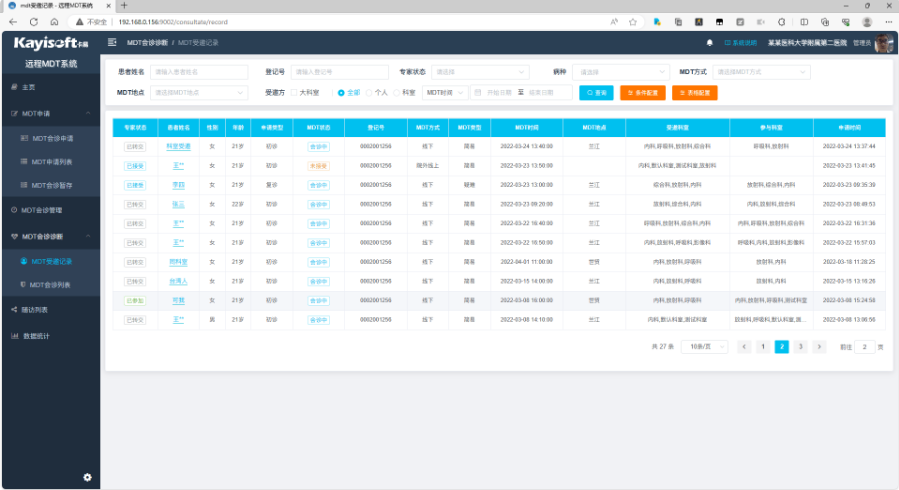

平台支持远程MDT、线下MDT等多种模式,申请医生提交MDT申请并提交患者相关信息后,专家团队通过线下MDT会诊、远程协同等方式,一体化浏览业务全部内容包括病历一般信息、影像检查、检验报告、电子病历、电生理等。支持MDT过程记录、MDT整体录音、MDT随访跟踪、MDT群聊、人脸识别签到、MDT报告撰写、修改、发布、MDT报告模板管理、ICD-10国际编码、互动式操作。